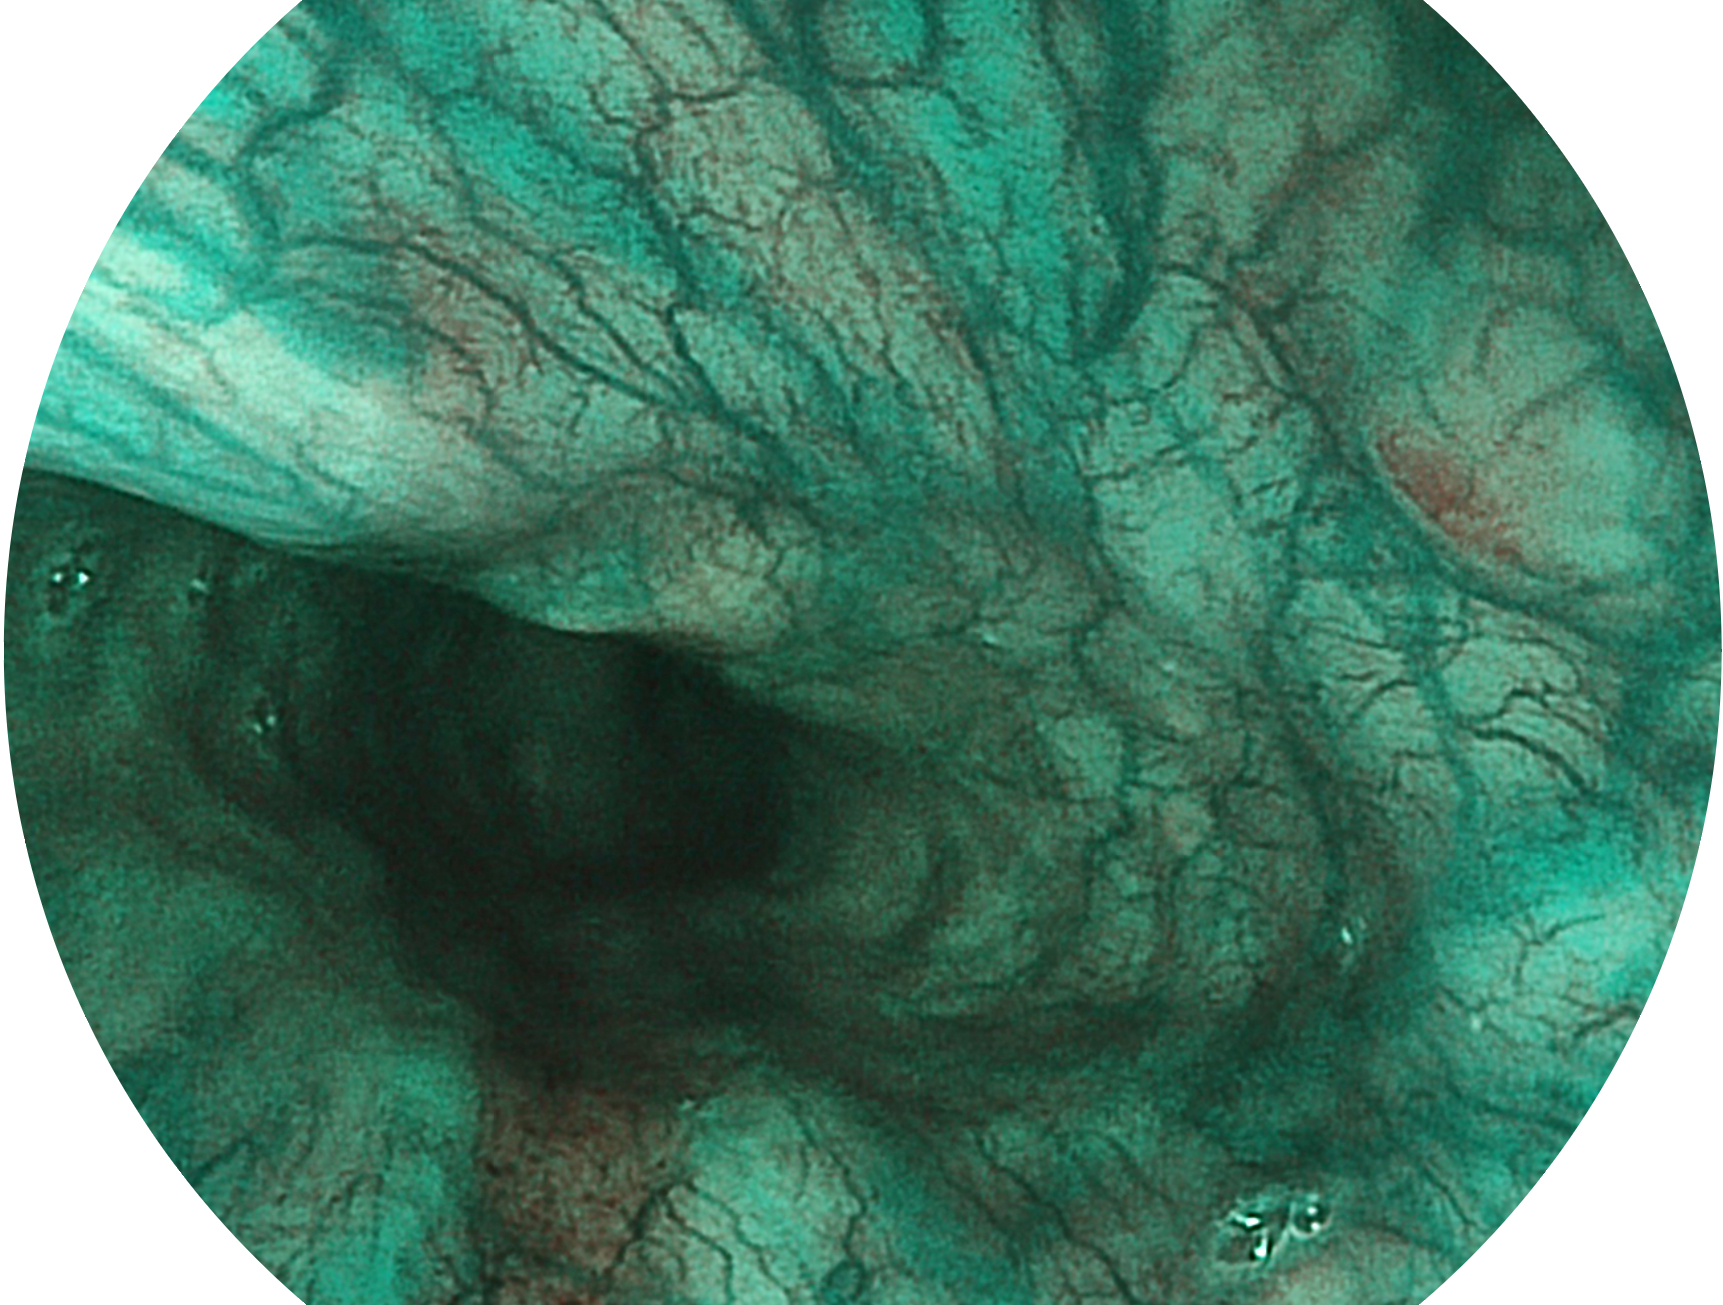

竞技宝(JJB)官方网站新开发的内镜染色技术,主要是基于多波长LED 光源的开发,VLS-55Q 四波长LED 光源是由四个不同颜色的LED光按照相应照明模式所规定的特定发光比例进行合束后形成,合束后形成的照明光的光谱由红光、绿光、蓝光及蓝紫光这四个不同的波段范围构成。具有更高光谱自由度,通过光谱比例的控制,实现了聚谱成像技术,英文全称为“Spectral Focused Imaging, SFI”,缩写为“SFI”和光电复合染色成像技术,英文全称为“Versatile Intelligent Staining Technology, VIST”,缩写为“VIST”。